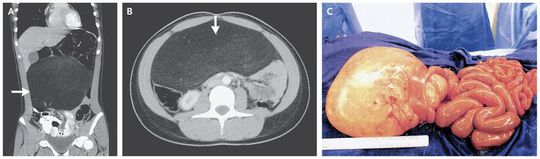

A 13-year-old girl with a history of abdominal discomfort was admitted with an acute onset of bilious vomiting. During the preceding weeks, the patient had reported having constipation, nausea, vomiting, and abdominal and back pain of increasing intensity. The patient’s vital signs were within normal limits. The physical examination revealed diffuse abdominal tenderness without guarding and no palpable masses. Plain radiography of the abdomen that was performed earlier the same day showed a nonspecific gas pattern but was otherwise normalComputed tomography performed without the use of contrast material showed a lesion measuring 19.5 cm by 16.6 cm by 8.8 cm that had characteristics of a lipoma. Liposarcoma could not be ruled out, since the lesion contained septations and encompassed the adjacent bowel (Panels A and B, arrows). The patient underwent resection of the primarily mesenteric tumor with adjoining bowel (Panel C). Results on pathological analyses were initially inconclusive; however, genetic sequencing confirmed the diagnosis of benign lipoma. Benign lipomas occur infrequently, especially in children, although patients who are obese or who have diabetes or a family history of lipoma are at increased risk. The patient, who had no known family history or associated risk factors, was discharged after an uneventful postoperative period, with no recurrence of symptoms at follow-up.